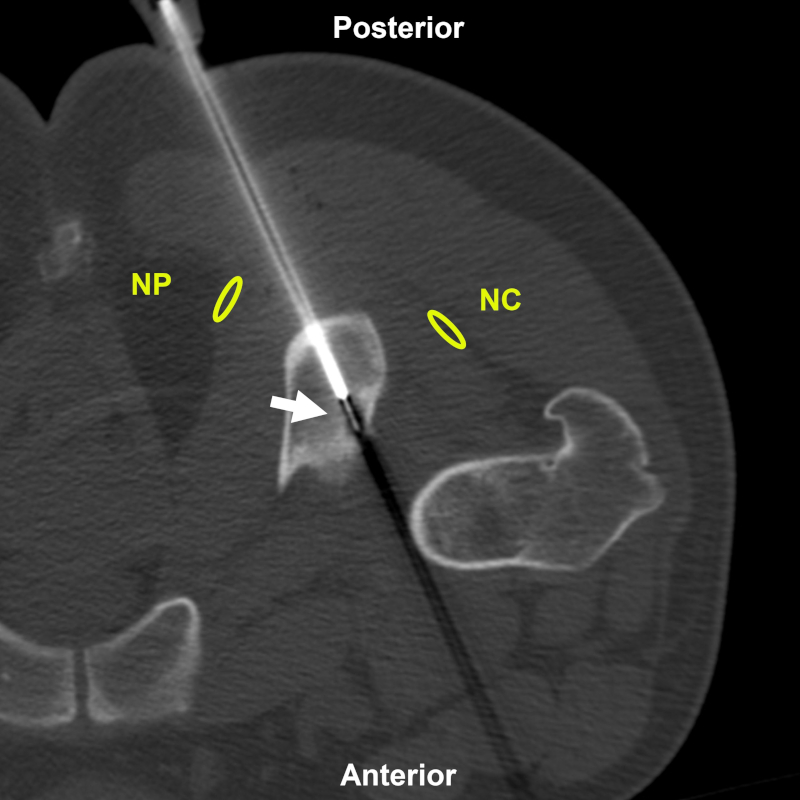

Figura 16

Varón de 22 años en plan de biopsia y ablación por radiofrecuencia de osteoma osteoide en la tuberosidad isquiática. Acceso coaxial posterior (flecha) guiado por TC. Estructuras a evitar: NC: nervio ciático; NP: nervio pudendo. Aguja utilizada: Jamshidi 11 G con electrodo de radiofrecuencia. Diagnóstico final: osteoma osteoide.